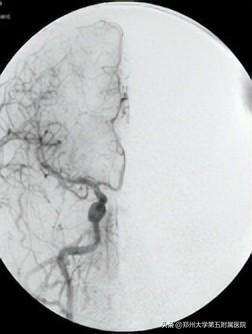

02CT (電子計算機體層攝影)

用X射線束對人體某部位一定厚度地掃描,根據人體不同組織對X線的吸收與透過率的不同,應用靈敏度極高的儀器對人體進行測量,然後將測量所獲取的數據輸入電子計算機,電子計算機對數據進行處理後,就可獲取人體被檢查部位的斷面或立體的圖像,發現體內任何部位的細小病變。它是通過數據計算得到的重建圖像。

雖然CT依舊用的是X射線,但不同於X光用的是X射線的螢光作用直接在攝影膠片或螢屏成像,CT則是通過數據計算得到的重建圖像。X線與CT檢查均有輻射!